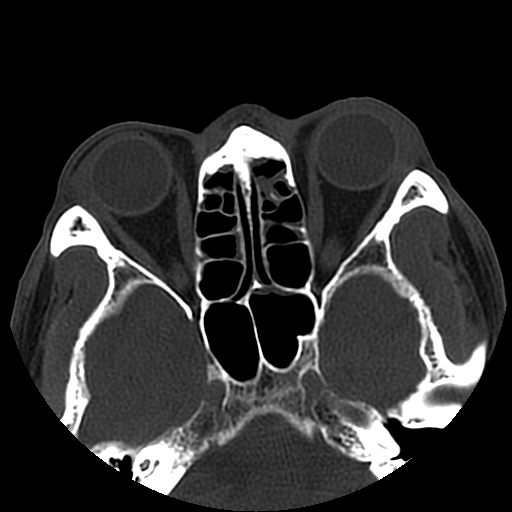

以下是引用liaoqiang在2008-7-16 21:15:00的发言:[br]右侧鼻骨骨折

以下是引用zxd95在2008-7-16 21:39:00的发言:[br]右侧上颌骨额突骨折。[br][br][br][br]